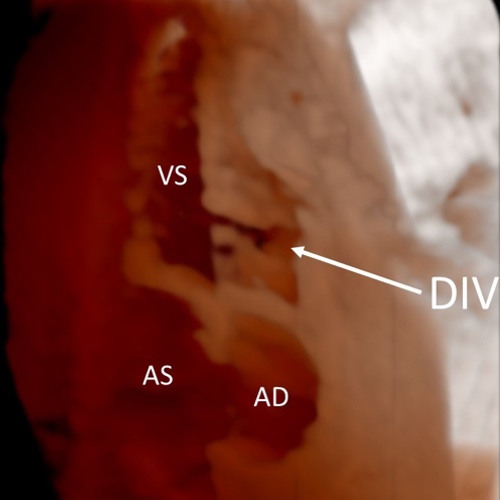

Ecocardiografia fetale - 22 settimane